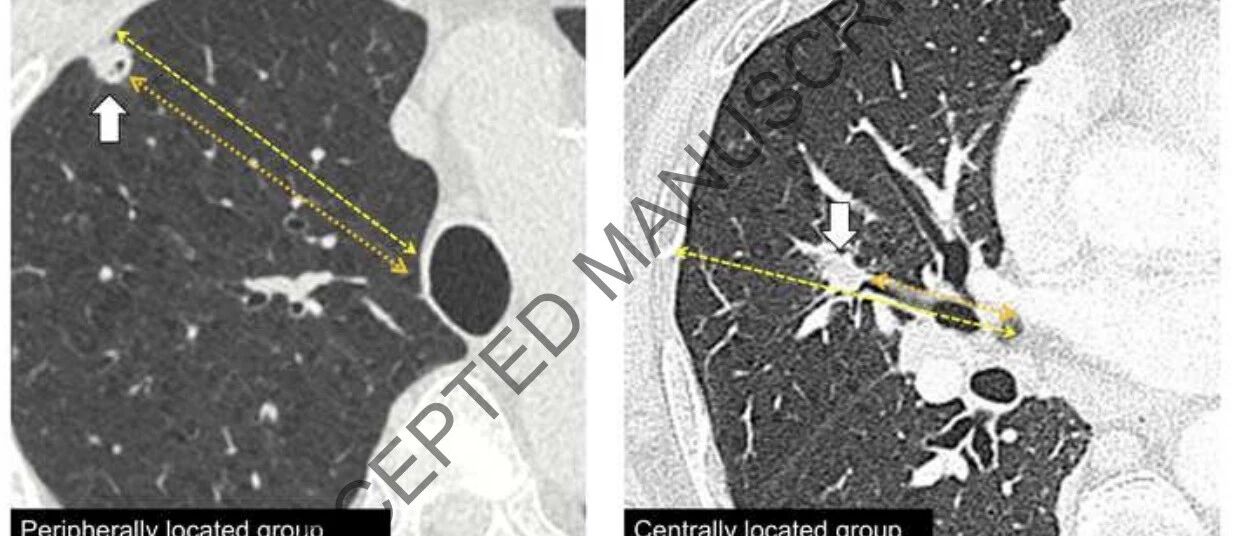

中央型I期非小细胞肺癌肺叶切除 vs 肺段切除